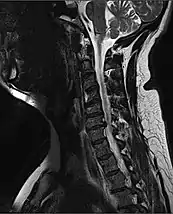

MRI of fractured and dislocated neck vertebra that is compressing the spinal cord

A radiographic evaluation using an X-ray, CT scan, or MRI can determine if there is damage to the spinal column and where it is located.[15] X-rays are commonly available[60] and can detect instability or misalignment of the spinal column, but do not give very detailed images and can miss injuries to the spinal cord or displacement of ligaments or disks that do not have accompanying spinal column damage.[15] Thus when X-ray findings are normal but SCI is still suspected due to pain or SCI symptoms, CT or MRI scans are used.[60] CT gives greater detail than X-rays, but exposes the patient to more radiation,[62] and it still does not give images of the spinal cord or ligaments; MRI shows body structures in the greatest detail.[15] Thus it is the standard for anyone who has neurological deficits found in SCI or is thought to have an unstable spinal column injury.[63]